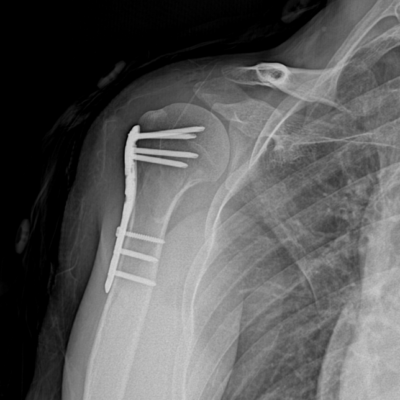

Shoulder Fractures

When surgery is necessary, Dr. Jang Sukhwan performs shoulder surgeries with over 20 years of experience, including 5,000+ arthroscopic procedures.

Common Procedures – Rotator cuff repair. capsular release (for frozen shoulder). calcium removal. labral repair. fracture fixation. etc.